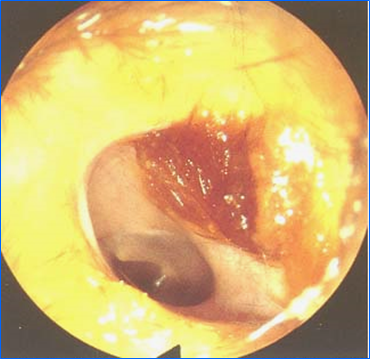

正常外耳道:软骨部外耳道有耳毛,覆有少量淡黄色盯聆碎片;骨性外听道的皮肤较薄而平滑,略淡红,无耳毛。